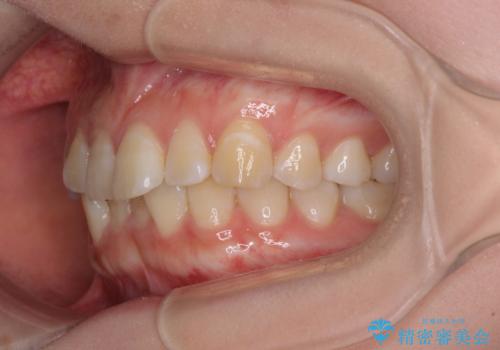

【モニター】前歯のデコボコを目立たないワイヤー装置で短期間矯正治療

- 上下前歯のデコボコを気にして来院された患者様です。

患者様も驚く、僅か10か月での治療終了となりました。

下顎前歯が1歯欠損しているため、上下正中は合わず、左右奥歯の咬み合わせは理想的とはならない仕上がりとなります。